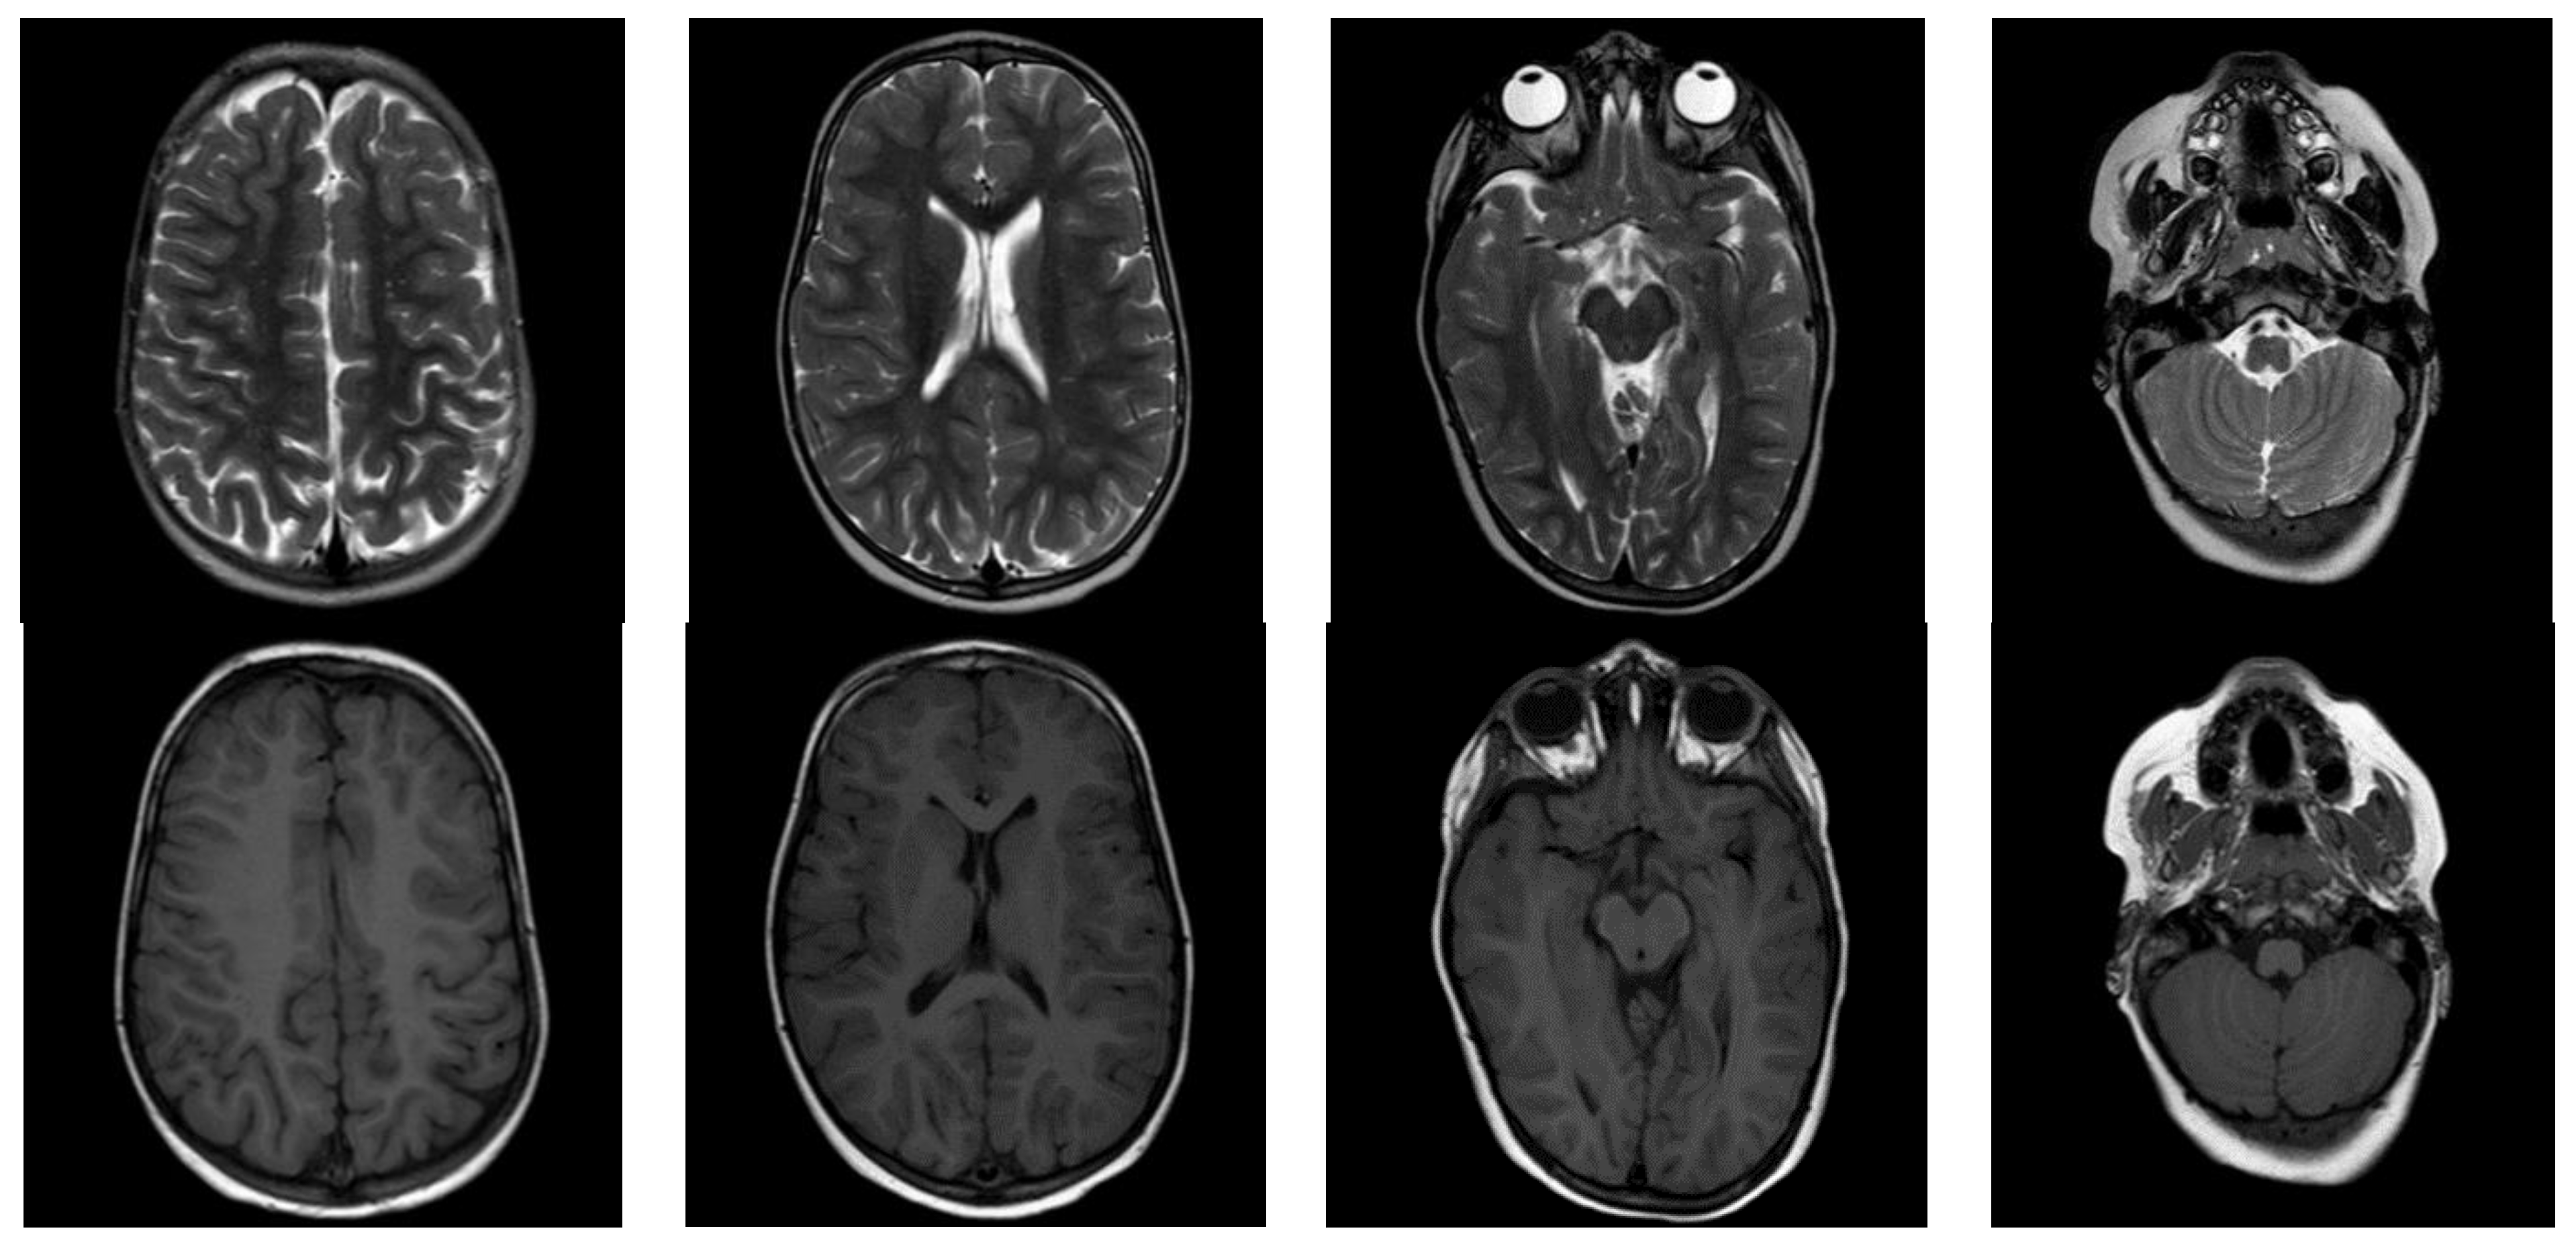

3.1. Case Report

3.3. Follow-Up